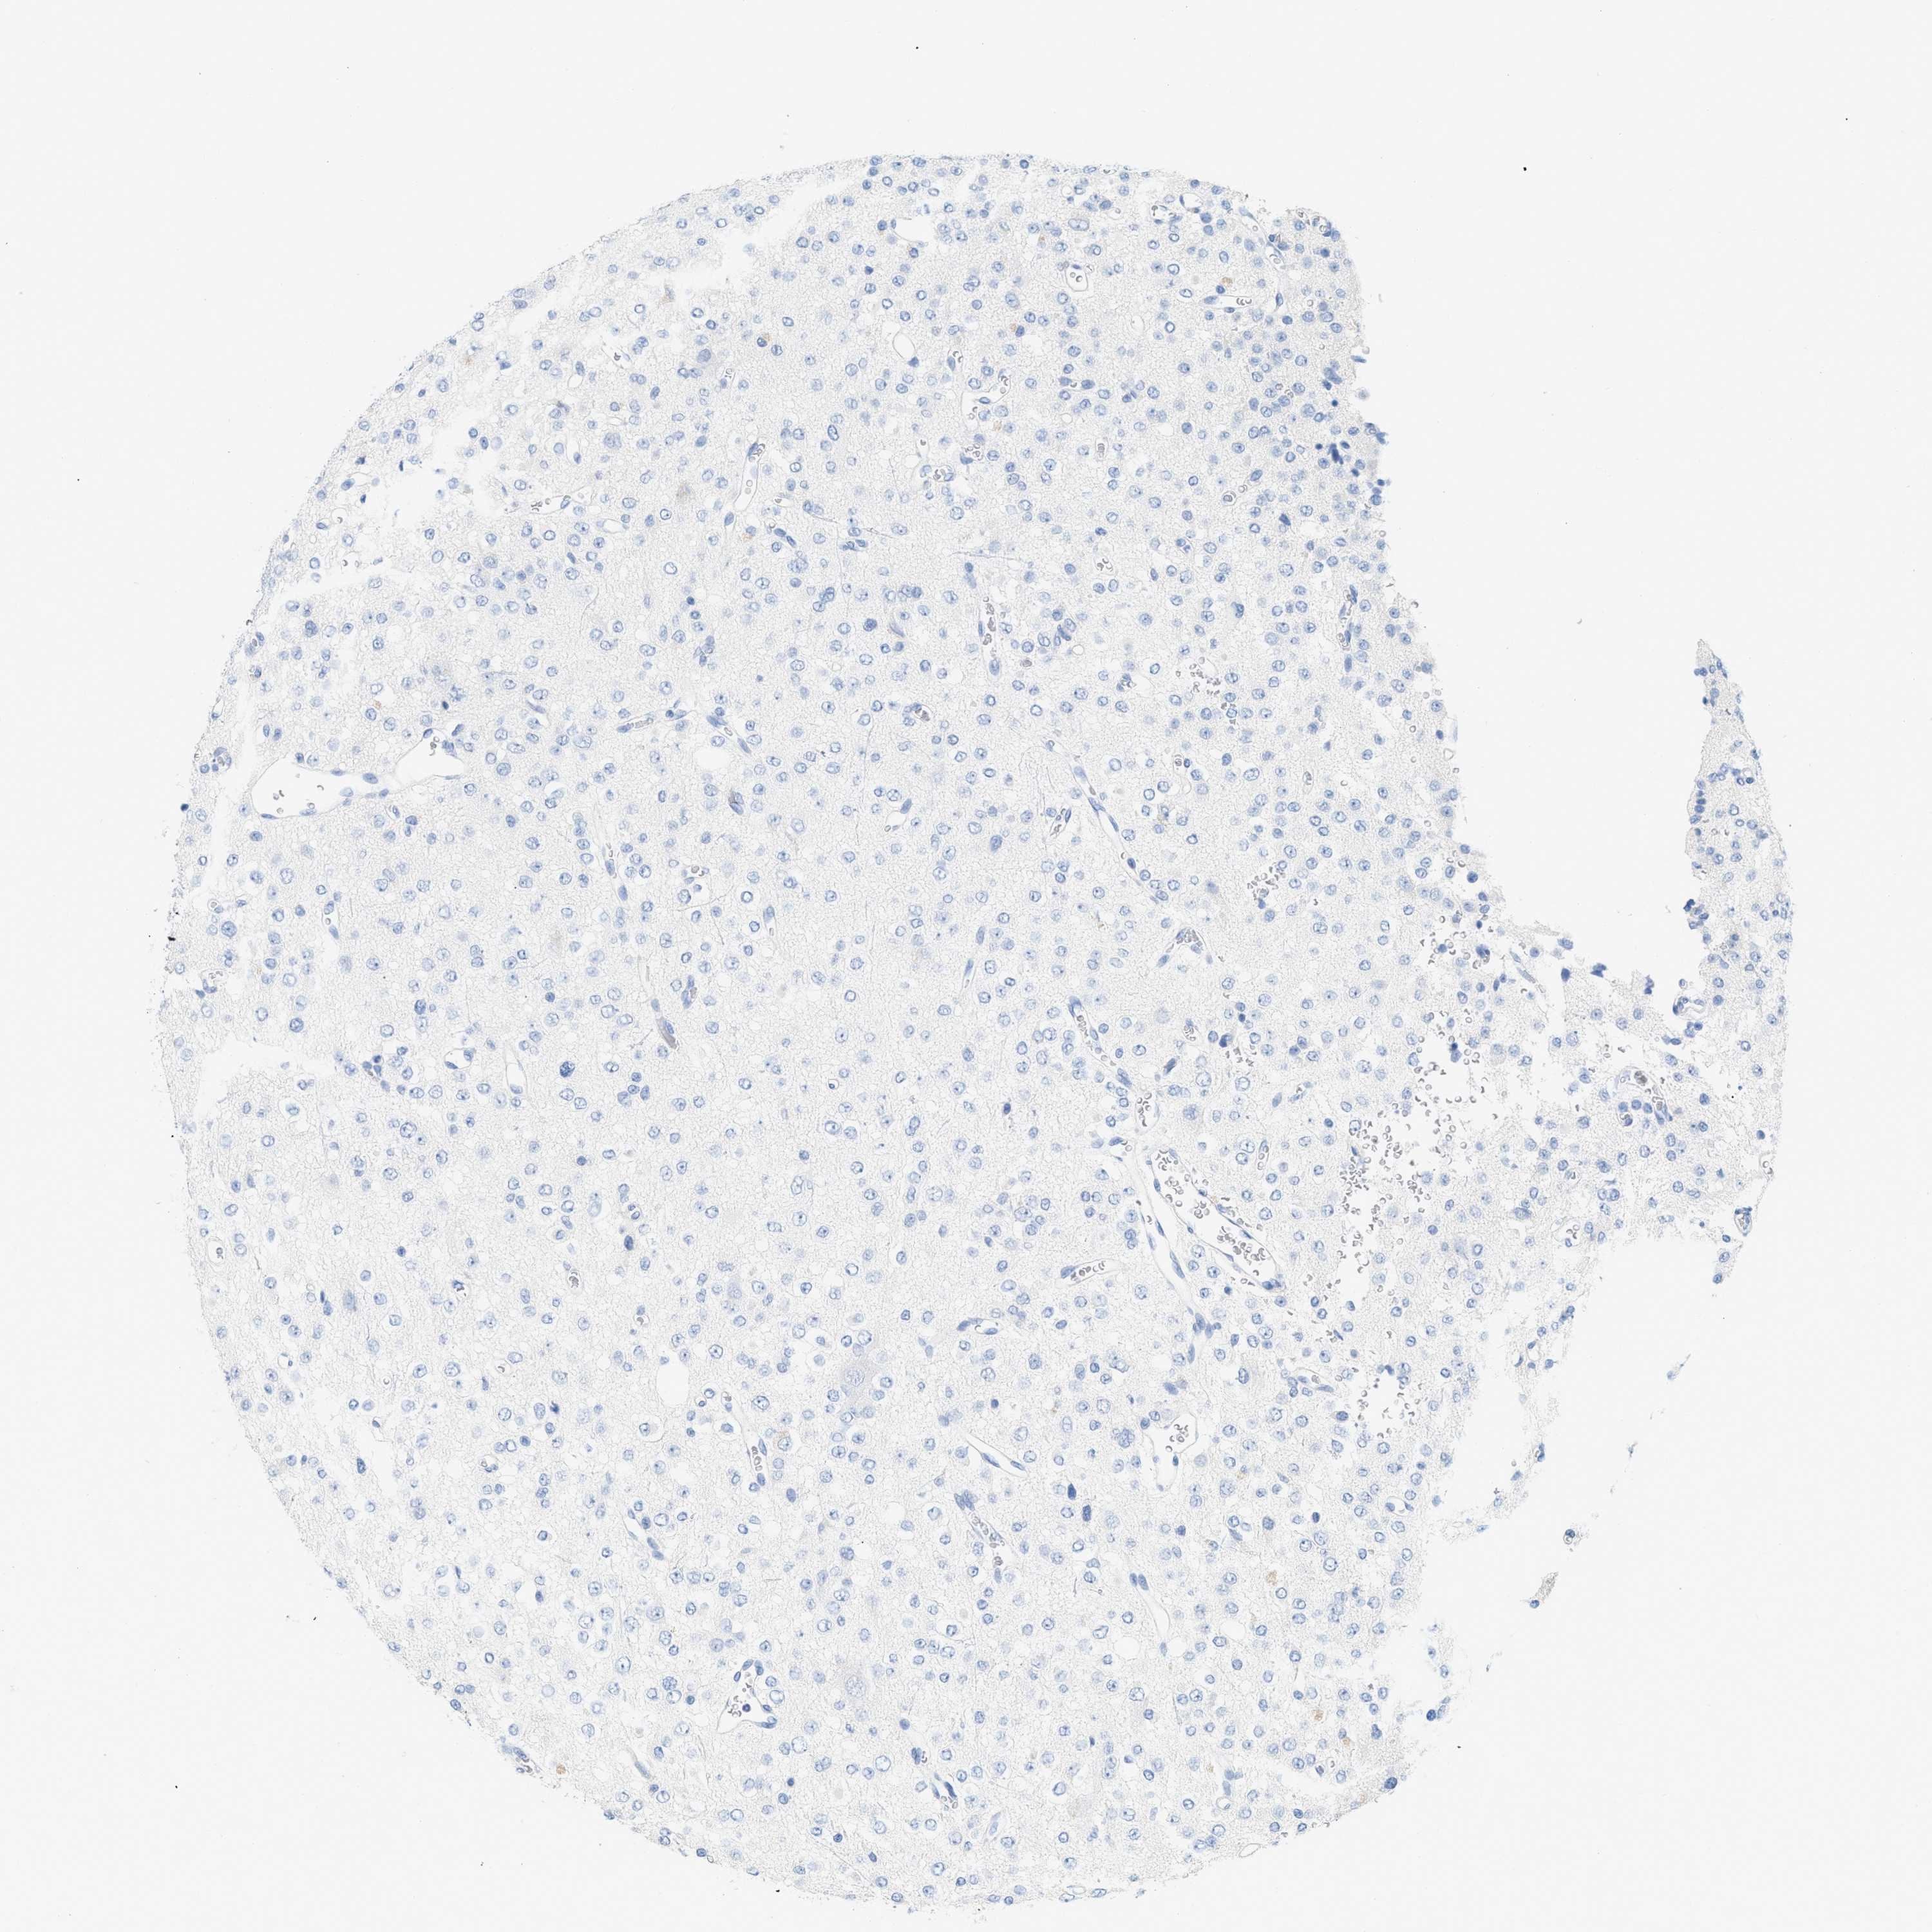

GLIOMA - Protein expressioni

A mouse-over function shows sample information and annotation data. Click on an image to view it in a full screen mode. Samples can be filtered based on level of antibody staining by selecting one or several of the following categories: high, medium, low and not detected. The assay and annotation is described here.

Note that samples used for immunohistochemistry by the Human Protein Atlas do not correspond to samples in the TCGA dataset.

Antibody stainingi

Antibody staining in the annotated cell types in the current human tissue is reported as not detected, low, medium, or high, based on conventional immunohistochemistry profiling in selected tissues. This score is based on the combination of the staining intensity and fraction of stained cells.

Each image is clickable and will lead to virtual microscopy that enables deeper exploration of all samples and also displays staining intensity scores, fraction scores and subcellular localization as well as patient and tissue information for each sample.

Antibody HPA001667

Antibody CAB016724

Staining

High

Medium

Low

Not detected

Intensity

Strong

Moderate

Weak

Negative

Quantity

>75%

75%-25%

<25%

None

Location

Nuclear

Cytoplasmic/membranous

Cytoplasmic/membranous,nuclear

Glioma, malignant, High grade

Glioma, malignant, Low grade

Glioma, malignant, NOS